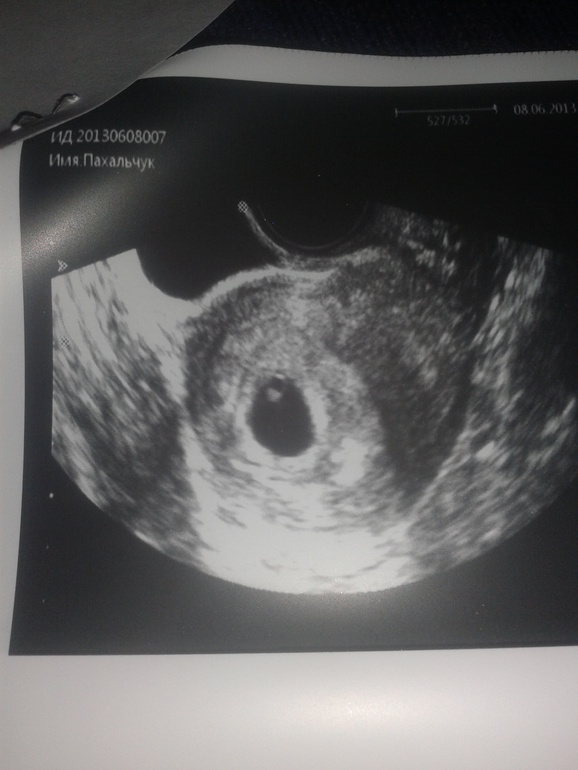

Первое узи и наша бусинка: